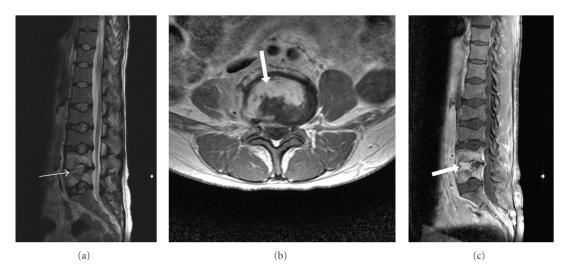

Sickle cell anaemia is an autosomal recessive genetic condition producing abnormal haemoglobin HbS molecules that result in stiff and sticky red blood cells leading to unpredictable episodes of microvascular occlusions. The clinical and radiological manifestations of sickle cell anaemia result from small vessel occlusion, leading to tissue ischemia/infarction and progressive end-organ damage. In this paper we discuss and illustrate the various musculoskeletal manifestations of sickle cell disease focusing primarily on marrow hyperplasia, osteomyelitis and septic arthritis, medullary and epiphyseal bone infarcts, growth defects, and soft tissue changes.

镰状细胞贫血是一种常染色体隐性遗传疾病,会产生异常的血红蛋白HbS分子,导致红细胞僵硬且黏附性增强,从而引发不可预测的微血管闭塞发作。镰状细胞贫血的临床和放射学表现是由小血管闭塞引起的,会导致组织缺血/梗死以及终末器官的进行性损害。在本文中,我们将讨论并举例说明镰状细胞病的各种肌肉骨骼表现,主要聚焦于骨髓增生、骨髓炎和化脓性关节炎、骨髓和骨骺骨梗死、生长缺陷以及软组织变化。